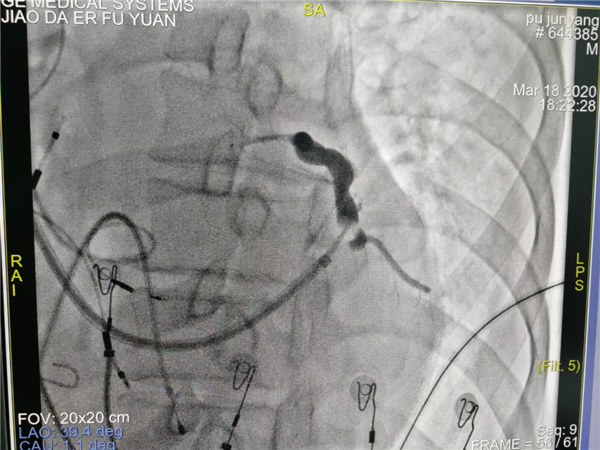

团队术前缜密讨论,充分考虑多个结局,多种策略。手术由郑强荪主任,韩振华副主任,薛嘉虹副教授,王新宏副教授及导管室护士王军、杨宏斌共同完成。团队先为患者行左心室电极植入冠状静脉窦的经典CRTD,但患者冠状静脉窦分支条件较差,左侧后支迂曲盘旋,给操作带来极大的困难,经多次尝试左室电极仍不能植入成功,郑强荪主任、韩振华副主任带领的团队迅速改变策略,与时俱进,决定行左束支区域起搏。另外患者在拔除原右室电极时又因电极与上腔静脉入口处粘连拔除困难,再次为手术带来障碍,最终经团队6小时的不懈努力,手术顺利完成。术后心电图QRS波群由原来的210ms缩窄为160ms,患者心功能明显改善。

术中冠状静脉窦造影